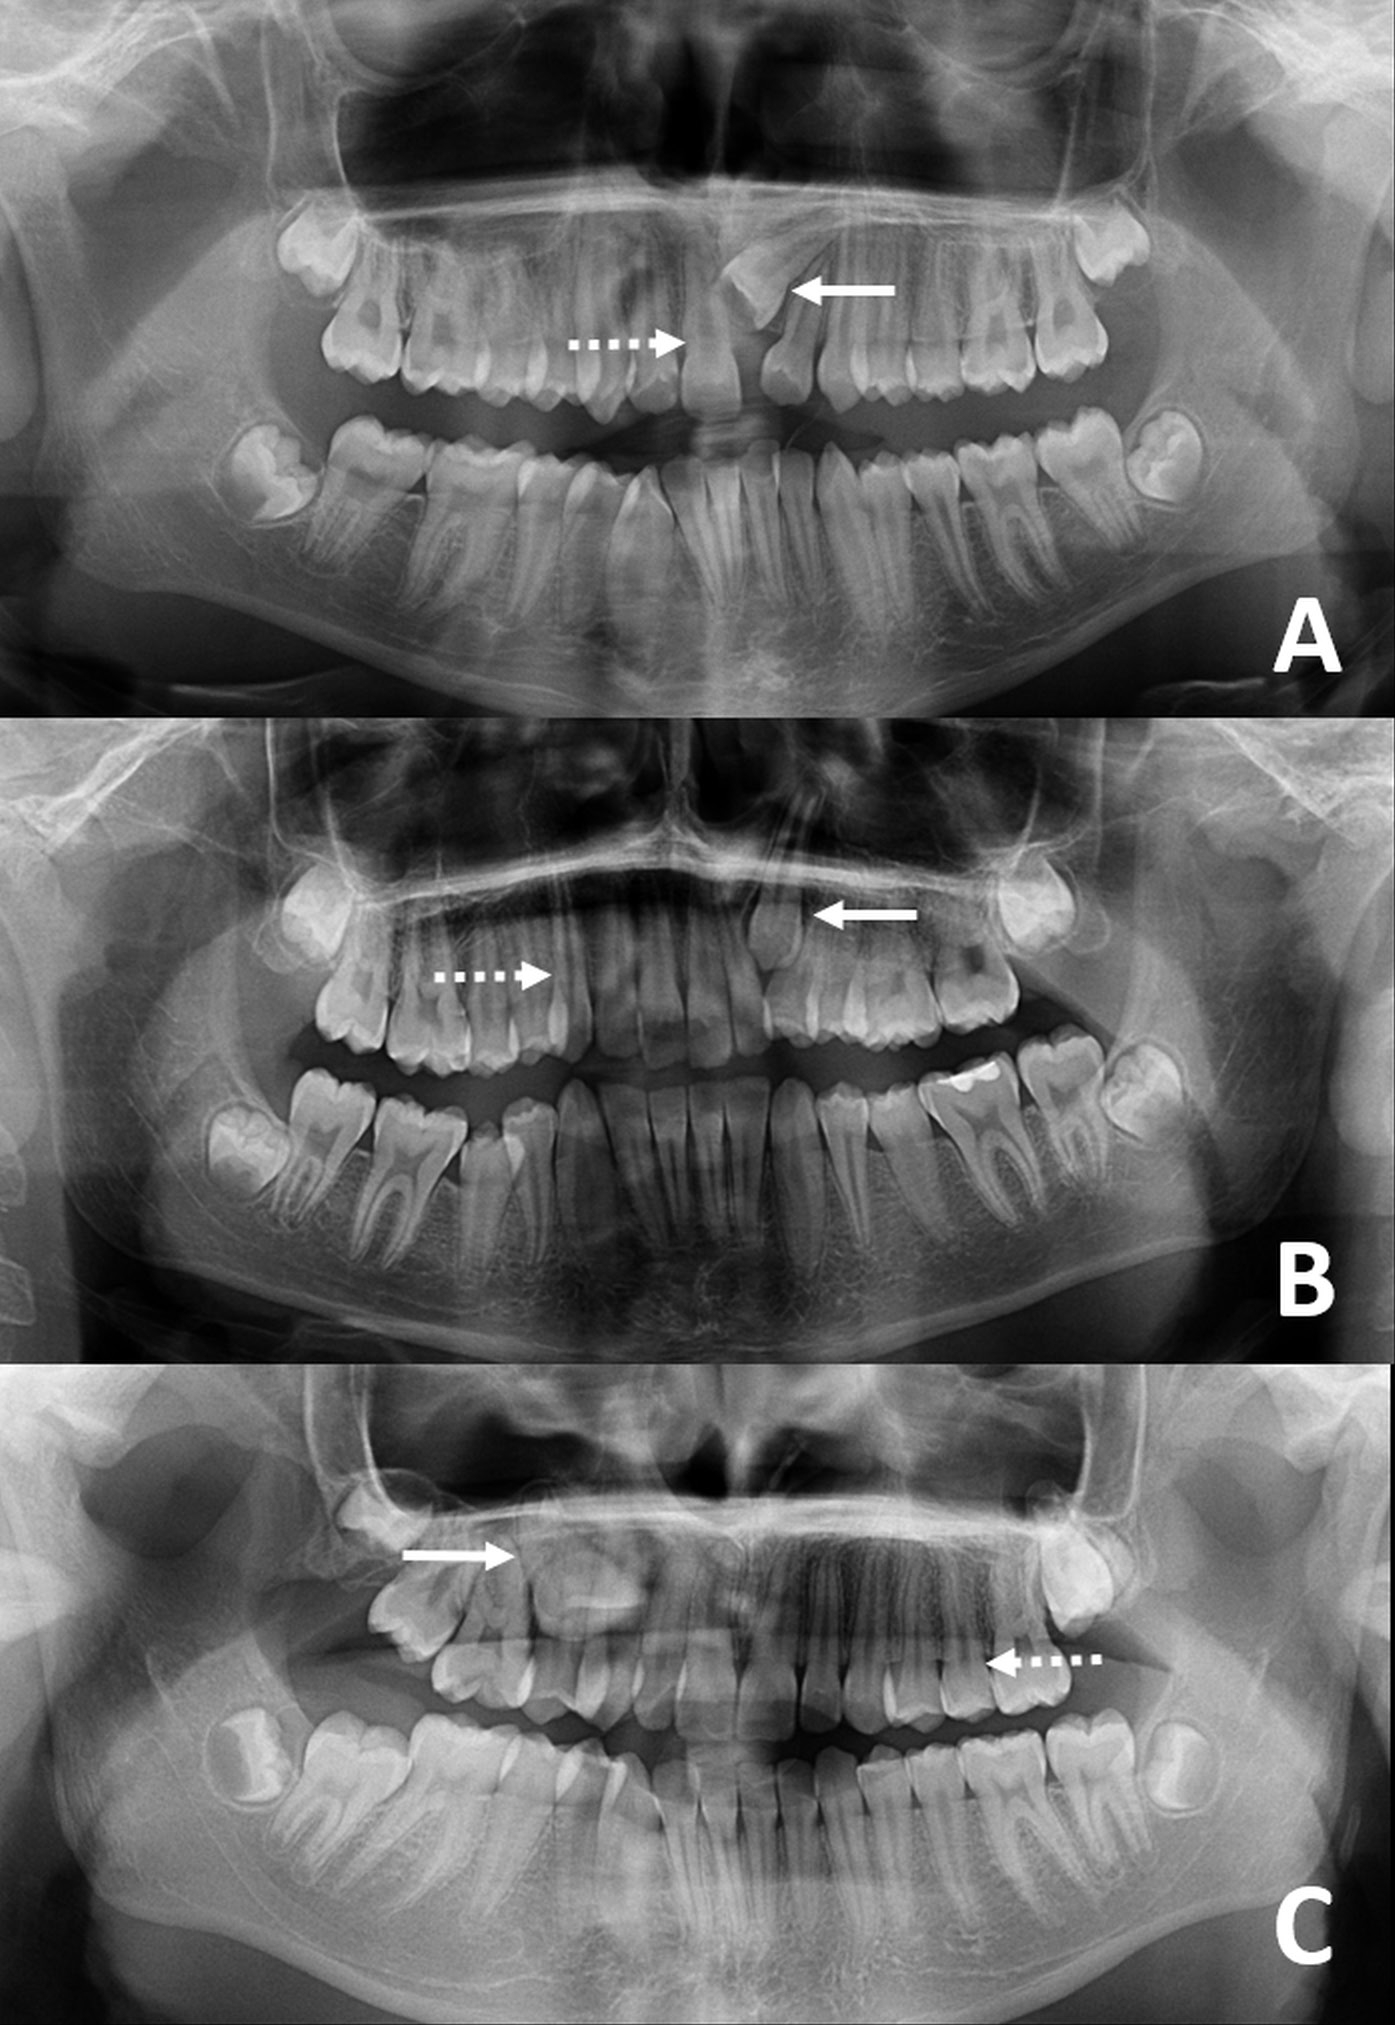

Two radiologists recorded each patient’s sex and chronological age in years and months, while a technician was responsible for taking all images. Firstly, panoramic radiographs were obtained from patients who had applied to our clinic for dental treatment. The CBCT images were taken if necessary, in the presence of impacted teeth or due to other dental reasons (1,598 patients). In order to be included in the study, patients had to be between the ages of 9 and 14 years, as determined by CBCT and panoramic images from 2014–2020, and must have had permanent dentition in the maxillary region. A total of 51 individuals were included in the study. The patients were not requested to undergo radiographic imaging for the study. Panoramic radiography results are depicted in Figure 1.

Patients with caries-affected teeth, teeth with pathological wear, coronal fracture, external and internal resorption, or teeth that had received general dental treatment for odontoma were excluded from the study. Patients with teeth exhibiting abnormal dental anatomy, which complicates measurement, were also excluded.